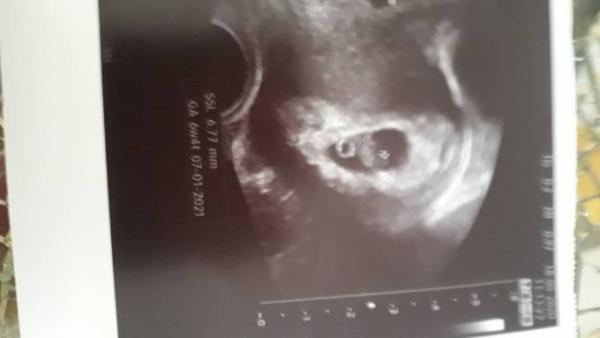

Hallo Mädels, komme grade von meinen Termin beim Frauenarzt zurück und was soll ich sagen, bin 6+4 meinen Baby geht es bestens und es Herz hat man heute auch kräftig schlagen gesehen. ET wurde auf 07.01. gesetzt Ich hoffe euch geht es allen gut und ihr dürft euch auch so freuen lg

Bild zu 1 Termin bam Doc - Forum für Januar - Mamis